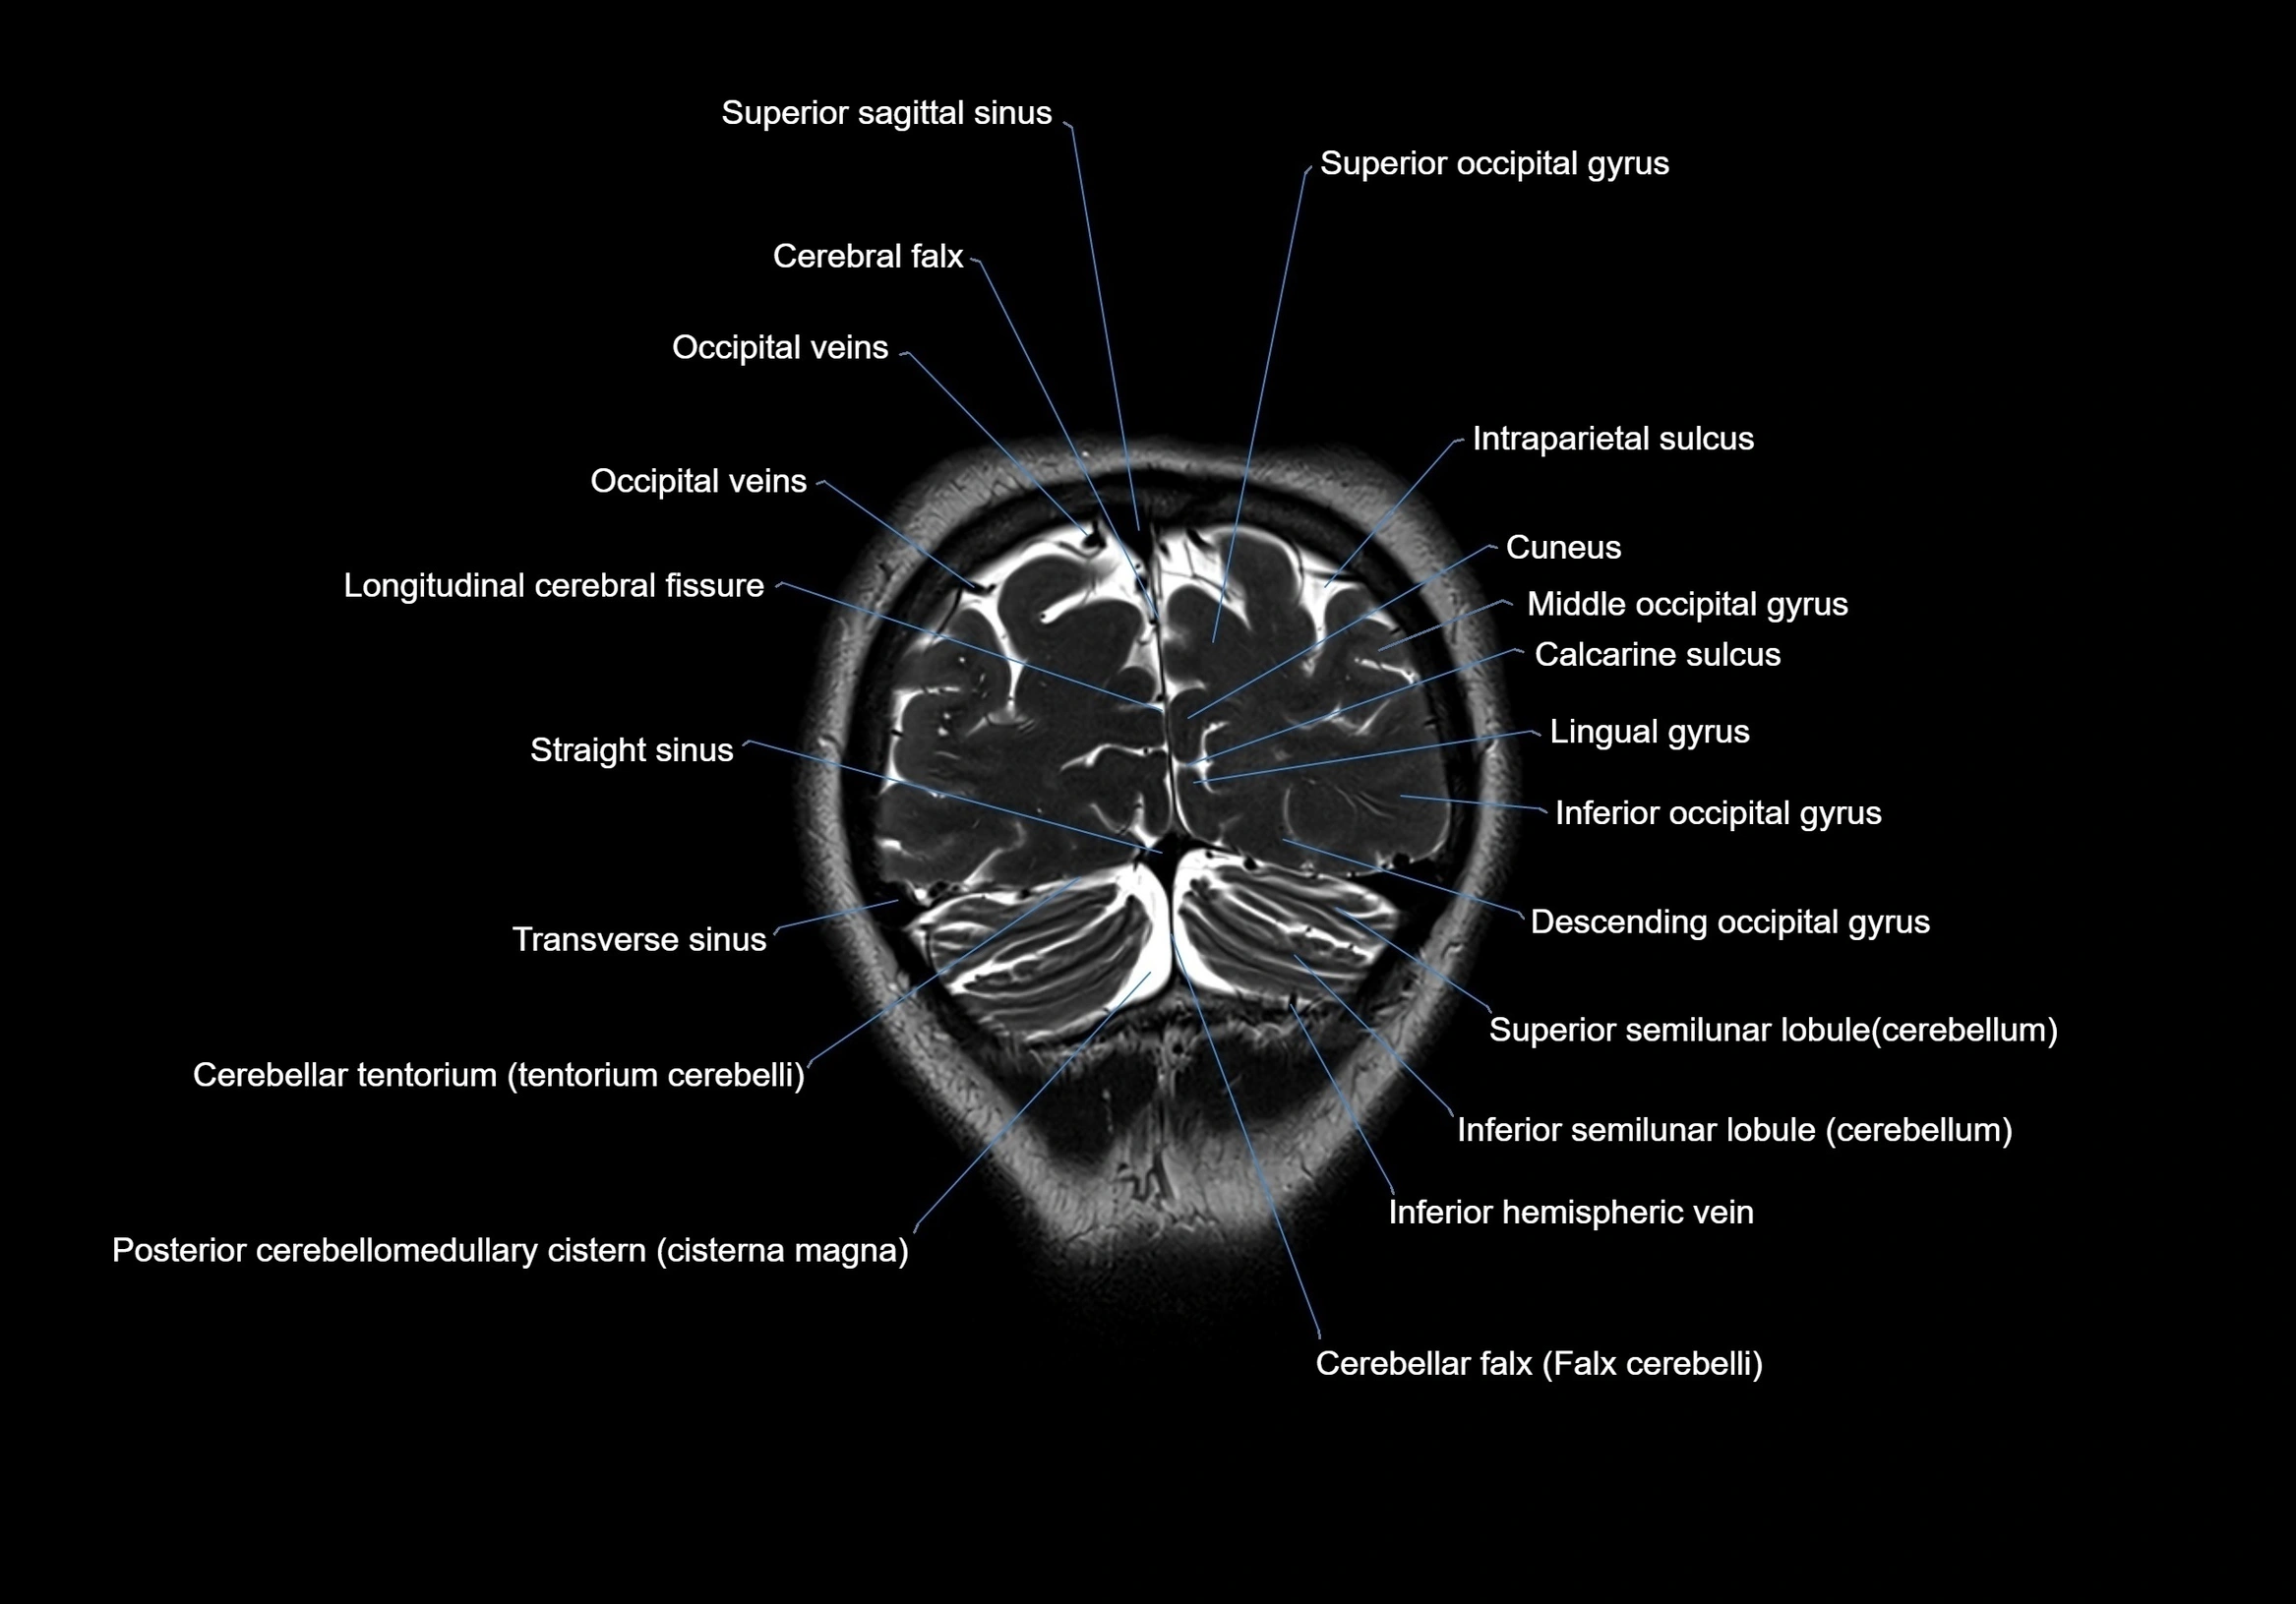

MRI images